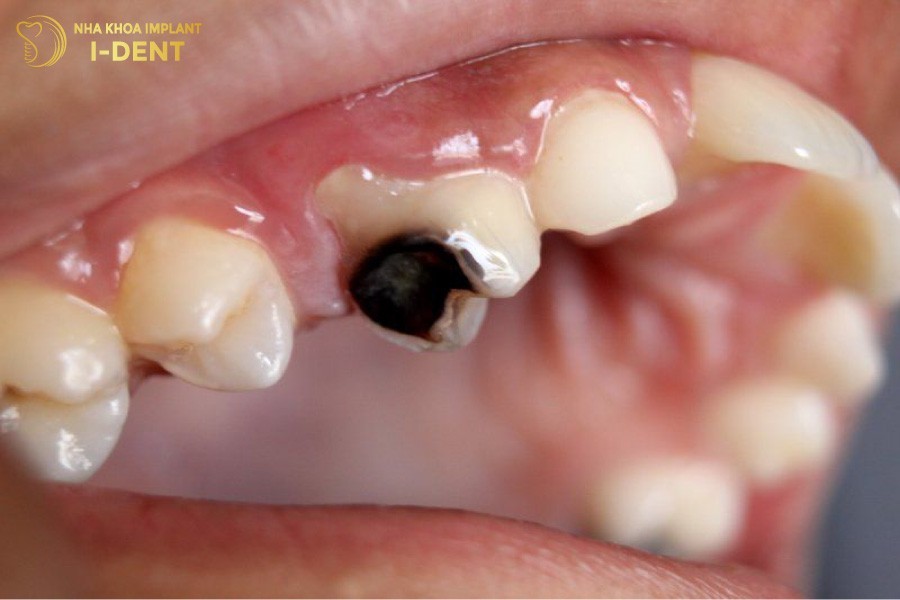

2.3 Sâu răng độ 3 ( Sâu đến tủy răng)

Trong các loại sâu răng thì mức độ sâu răng độ 3 được cảnh báo là nguy hiểm đến sức khoẻ nhất.

Khi bạn có thể cảm nhận những cơn đau nhức, thậm chí đau dữ dội lúc về đêm thì có nghĩa là tình trạng bệnh của bạn đã chuyển sang mức độ sâu răng nặng. Vi khuẩn sẽ ăn sâu vào vị trí đáy chân răng, hình thành ổ viêm nhiễm và gây ra tình trạng viêm tủy răng. Đây là nguyên nhân chính làm tăng nguy cơ áp xe răng, sâu răng hàm nặng, thậm chí là mất răng, nhiễm trùng máu.

Sâu răng độ 3 ( Sâu đến tủy răng).

Khi sâu răng đã diễn biến đến mức độ nghiêm trọng, bạn cần đến khoa để nha sĩ xử lý kịp thời. Nếu như chân răng chưa bị vi khuẩn tấn công đến, bác sĩ sẽ áp dụng phương án trám răng để phục hồi vết sâu. Còn nếu tủy răng đã bị phá huỷ nhiều thì bác sĩ sẽ chỉ định nhổ bỏ răng để tránh nhiễm trùng xương hàm.